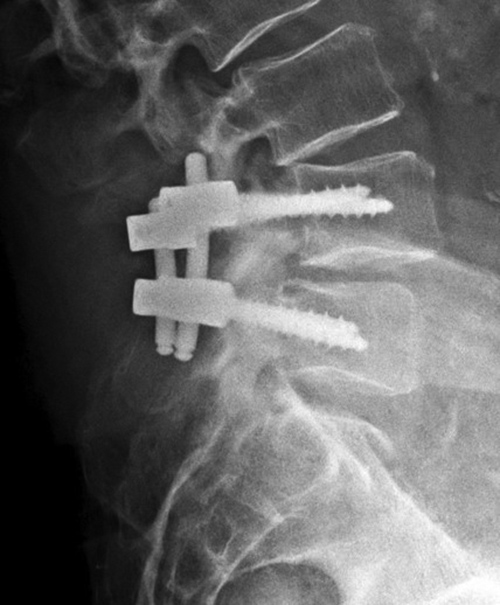

Harms vertebral cage (lateral view) |

| There is a vertebral cage and side plate and screws in the lower thoracic spine for treatment of a spinal tumor. From Hunter, 1994 |

| Vertebral corpectomy with vertebral cage and left lateral side plate |